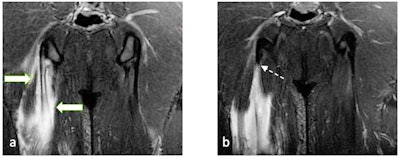

"Pelvic apophyseal injuries are common in young football players," stated Furtado and Zeitoun. "Apophyses, bony attachments of the tendons, are a common site of acute avulsion secondary to forceful muscle contraction. This might affect the anterior superior iliac spine, anterior inferior iliac spine, ischial tuberosity, iliac crest, and pubic bones, as well as the greater and lesser trochanters of the femur."

Continuous muscle traction exerts stress on the growing bone, resulting in chronic forms of injuries like in ischial apophysitis and osteitis pubis, they continued. These chronic injuries are a source of chronic pain that might affect training and generate concern, especially in young players at the start of their career.

"X-ray is good at demonstrating bone changes in chronic cases, while MRI is more helpful demonstrating bone edema at the anatomical site of tendon attachment and further revealing aponeurotic, tendon, and myotendon injuries," the researchers pointed out.